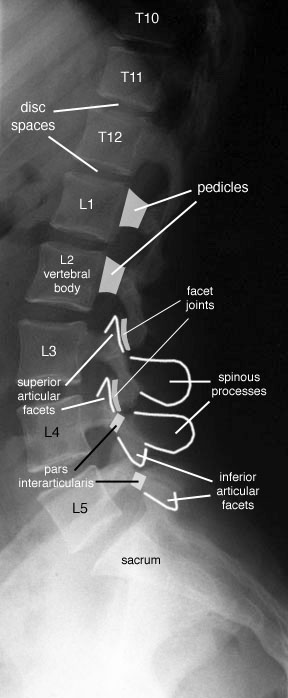

Tu peux analyser les lames sur le cliché de profil pour le rachis cervical, dorsal et lombaire ainsi que sur l’incidence de ¾ de lombaire où tu déroules les chiens de la chapelle

Les pédicules tu les analyses en coupe optique sur les incidences de face et sur le profil

Rachis cervical:  Rachis dorsal: Rachis dorsal:  Rachis lombaire: Rachis lombaire:   1. Processus articulaire supérieur 2. Pédicule droit 3. Processus transverse droit 4. Isthme 5. Processus articulaire inférieur 6. Lame opposée 7. Processus transverse opposé 8. Epineuse 9. Interligne articulaire postérieure 10. Processus articulaire inférieur opposé 11. Processus articulaire supérieur opposé Pour ce qui est de la radioanatomie; nous te laissons le soin d'apprendre tout cela grâce aux livres à ta disposition et à tes stages surtout!  Nous avions commencé une liste de livres de radiologie; à toi de t'en servir et bonnes recherches! Si tu souhaites trouver d'autres correspondances, si quelques détails t'interpellent n'hésite pas à poser des questions précises! Bon courage la marmotte!